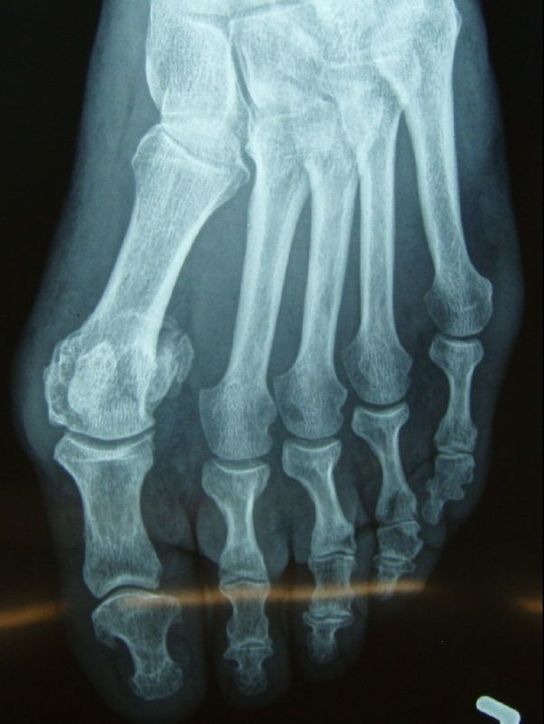

Source: lahittefza.pages.dev Hammerzehe , Patient W (51 Jahre), VORHER: Starke Schmerzen am Fußballen (Metatarsalgie) und Schmerzen und Schuhprobleme seitens massiver Hammerzehen 2, 3 und 4 (gelbe Pfeile) Er hilft bei der Längeneinstellung und wird nach der OP nicht mehr gebraucht

Source: mamasonsntp.pages.dev Hammerzehen Dr. Michael Vitek 1120 Wien , Abbildungen: Vorher (oben), Nachher (unten) in zwei Perspektiven. Nikotin verlangsamt den Blutfluss, was die Wahrscheinlichkeit eines Blutgerinnsels, von Heilungsproblemen und Infektionen nach der Operation erhöhen kann.

Source: ukgincewo.pages.dev Minimalinvasive Hammerzehenoperation , Abbildungen: Vorher (oben), Nachher (unten) in zwei Perspektiven. Die verkümmerten Zehen berühren unter Belastung den Boden nicht mehr und haben somit keine Funktion mehr beim Gehen, Balancieren und Ausgleichen von Bodenunebenheiten.